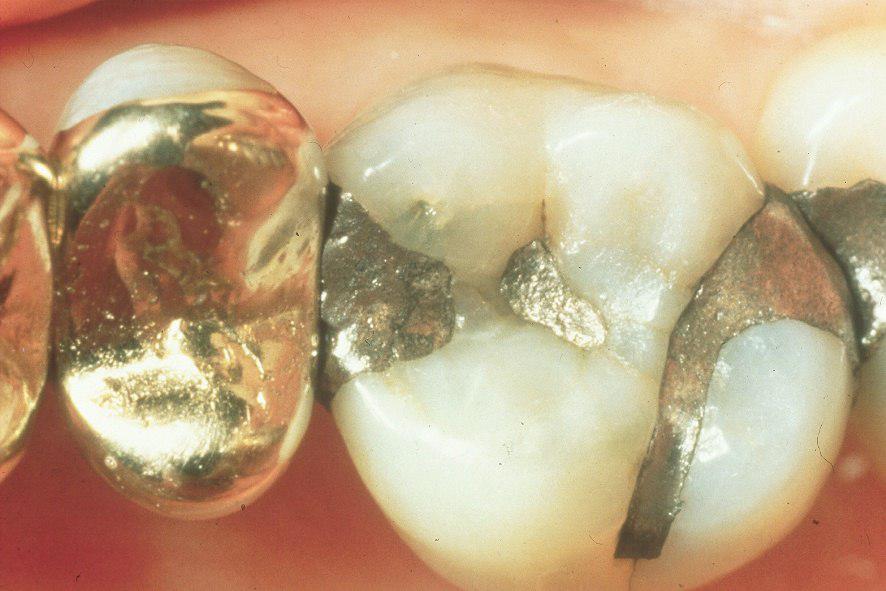

Аноним Срд 19 Мар 2014 01:15:56  #103 №64595407

>>64595338

Бросиь "после" еще

Аноним Срд 19 Мар 2014 01:16:48  #104 №64595451

1395177408818.jpg